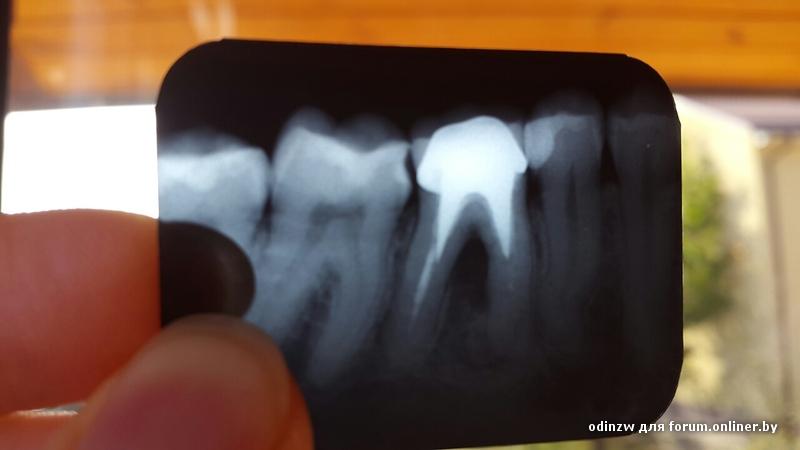

Здравствуйте! Имеется залеченный зуб с коронкой. Между корнями очаг воспаления. Вопрос к уважаемым специалистам: есть ли шанс перелечить зуб? Какова вероятность удачного лечения? Если есть шанс удачного исхода, то куда в Минске можно обратиться за помощью?

odinzw, это показание на удаление

odinzw:

Лучше не тратить деньги зря, а удалять и имплант.